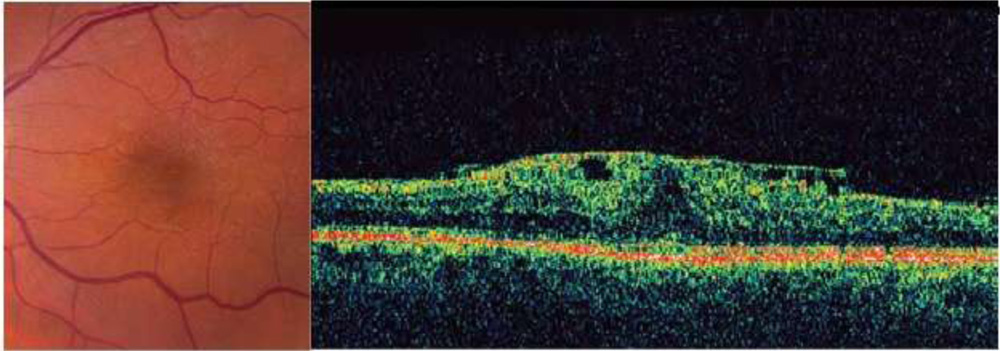

(a) ERM following cryotherapy of a peripheral retinal break. (b) OCT showing highly reflective ERM, corrugation of retinal surface, loss of foveal depression, and increased central macular thickness

OCT can play an important role in the clinical assessment of eyes with ERMs.

OCT can not only detect ERMs, but also assist in topographic localization, identification of vitreoretinal relationships (such as in the vitreomacular traction syndrome), detection of macular holes, and quantitation of macular thickness and macular volume.

Fig. OCT showing typical ERM features including highly reflective ERM, multiple points of retinal attachment, loss of foveal depression, and increased retinal thickness.